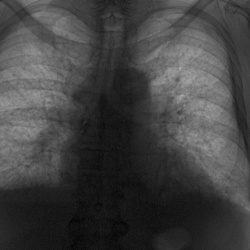

Женнщина 60 лет. Диагностическая флюорография. Состояние после аллопластики диафрагмы (ГПОД) в конце сентября. Диафрагма слева приподнята, жидкость в прямой проекции видна, а на боковой -  нет....